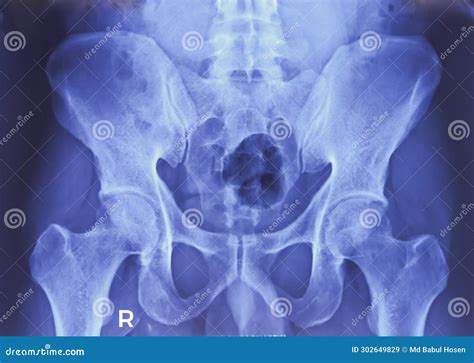

• Imaging studies, such as X-rays, MRI, or CT scans, to visualize the joint and surrounding structures

In some cases, an Xray Si Joint may be recommended to confirm the diagnosis and rule out other potential causes of pain. This imaging technique provides detailed images of the joint and can help identify any abnormalities or degenerative changes.